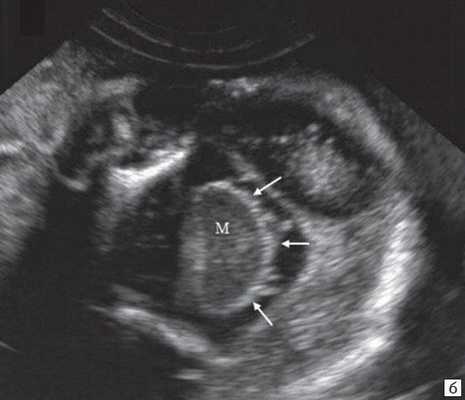

При изучении анатомии головного мозга плода в режиме 2D с применением стандартных аксиальных срезов во всех наших случаях мозжечок выглядел в виде овального образования однородной структуры с поперечным размером, менее уровня 5 процентиля для соответствующего срока беременности. При этом отсутствовала межполушарная выемка и область повышенной эхогенности по срединной линии мозжечка, характерная для отражения червя (рис. 1). На коронарном срезе также обращала внимание округлая однолобарная форма гипоэхогенного мозжечка (рис. 2). Использование трансвагинального подхода позволяло визуализировать дополнительно волокнистые структуры субарахноидального пространства (рис. 2).

Рис. 2. Корональные срезы головного мозга плода. Показан овальный контур мозжечка и волокнистые структуры субарахноидального пространства (стрелки).

а) Наблюдение 1, 3D.

б) Наблюдение 4, трансвагинально.